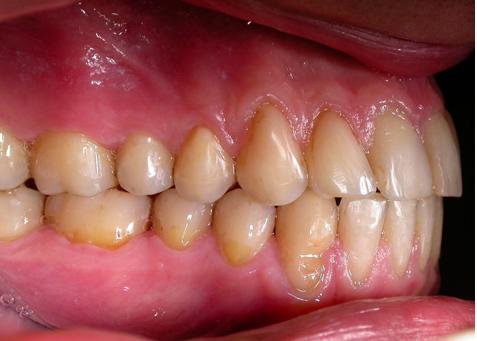

Пациент обратился с диагнозом индивидуальная макродентия.

Диагностика дополнительно выявила:- тенденцию к формированию мезиальной окклюзии,

- сужение и укорочение зубных рядов,

- ретрузию верхних центральных резцов,

- мезиальное смещение боковых отделов нижнего зубного ряда,

- ретрузию нижних резцов,

- множественные аномалии положения зубов.

Лечение проводилось с апроксимальной сепарацией эмали зубов. Применялись керамические брекеты.

Результат получен спустя 18 месяцев после начала лечения